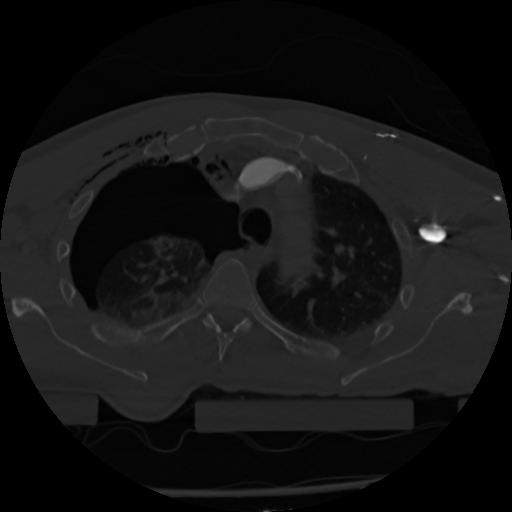

22 ANGIO,CE,Vol,0.5,ANGIO,,